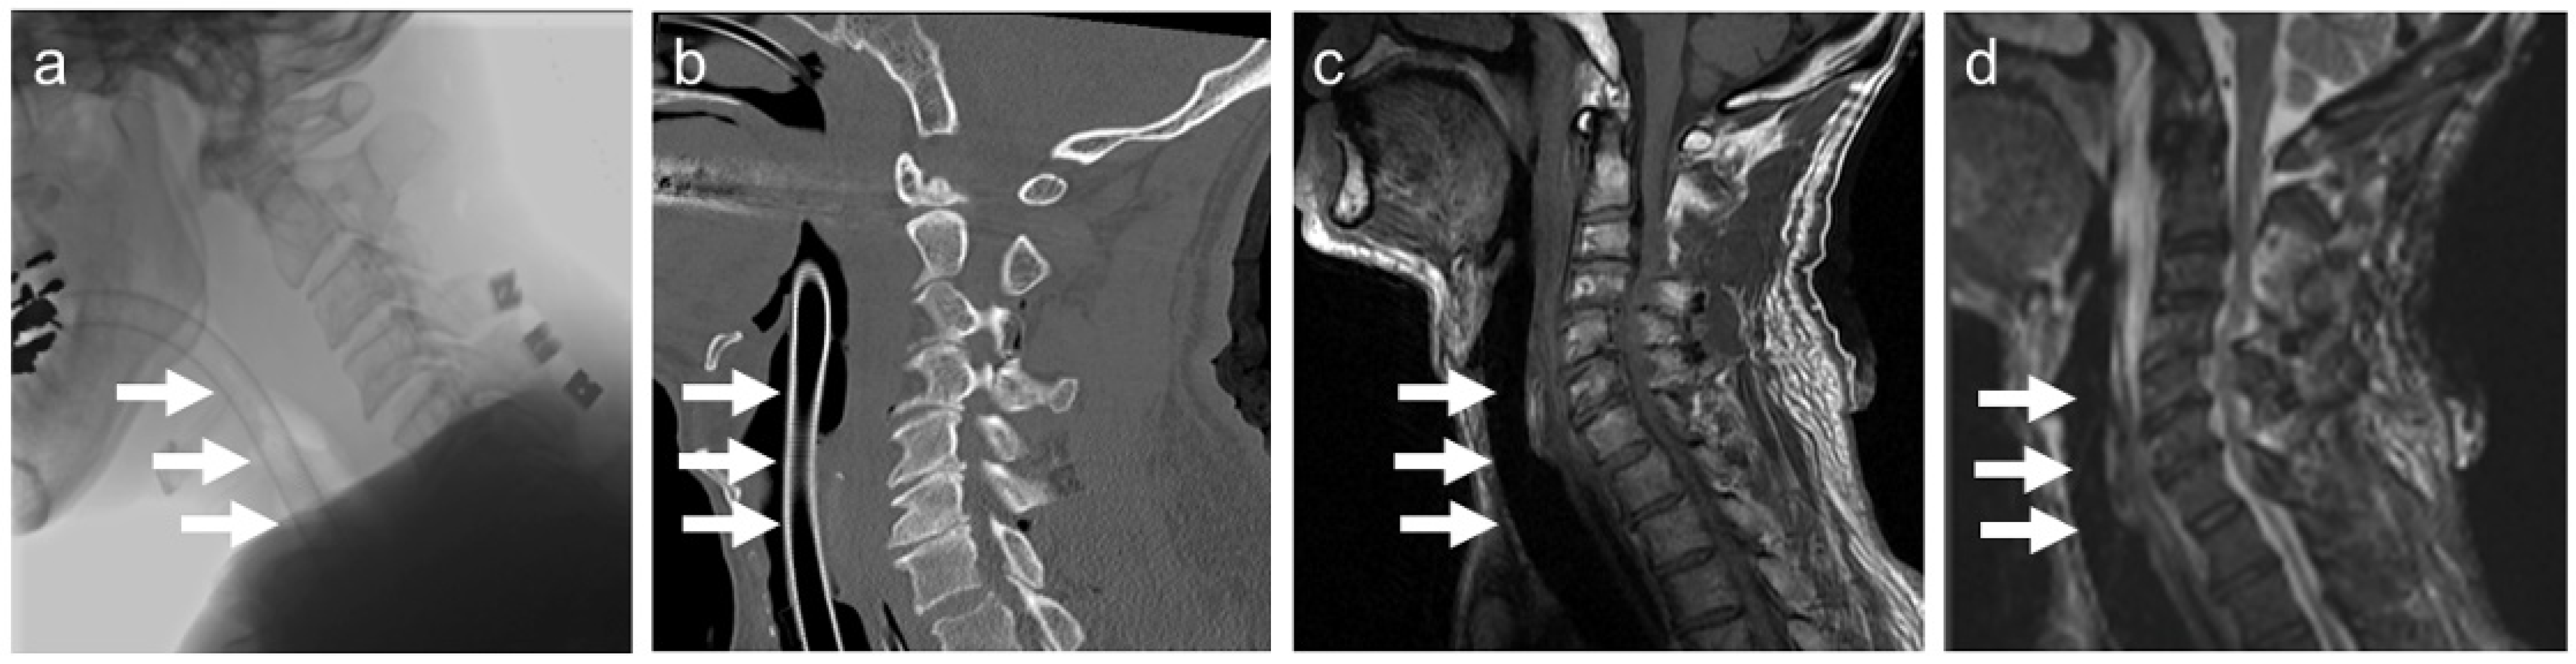

A representative image of a patient undergoing endotracheal intubation using the Ti-rET is shown in Figure 5. The patient was a 66-year-old man who was transferred to our hospital because of a motorcycle accident. He showed tetraparesis and respiratory failure due to severe cervical spinal injury. An in-line stabilization was applied while intubating the patient with a Ti-rET. Under the general anesthesia, we performed C3 laminectomy and C4–6 laminoplasty for decompression in the prone position. Ti-rET provides minimum artifact while performing CT and MRI examinations, and images of severe cervical spinal cord injury with severe cervical canal stenosis were obtained (Figure 5a–d).

Figure 5. Clinical use of the Ti alloy helical wire-reinforced endotracheal tube (Ti-rET). (a) Radiographic image, (b) sagittal computed tomography image, (c) sagittal T1-weighted MR image, and (d) sagittal T2-weighted MR image. The white arrows show the intubated Ti-rET.

All patients were intubated with a single intubation procedure. A Mcintosh laryngoscope was used in 5 cases, except for the case in which McGrath was used for preoperative Mallampati classification of Class III. No other assistive devices for endotracheal intubation were used during intubation. The Ti-rET was clearly delineated on radiography, and metal artifacts were small on computed tomography (CT) in the patients intubated with the Ti-rET. In addition, patients intubated with the Ti-rET could undergo MRI under sedation without adverse events in airway and respiratory management, and clear MR images without remarkable susceptibility artifacts were obtained. We observed no complications related to the Ti-rET in any of these intubations.